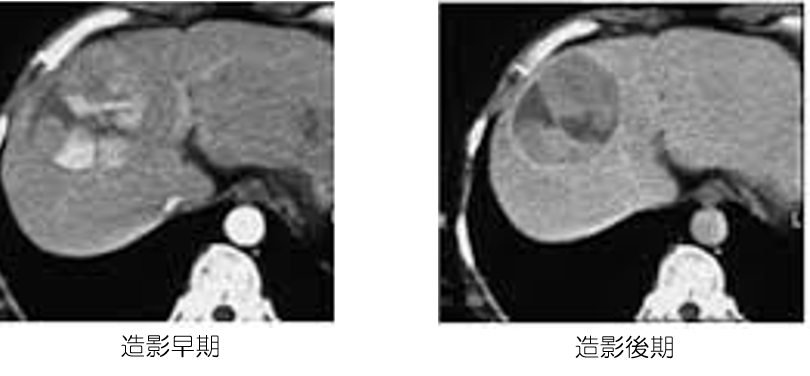

《肝細胞がん》

約80%がB型やC型の肝炎ウイルスが原因です。最近では、アルコール摂取過多、糖尿病や肥満などの生活習慣から肝細がんが発生することが増えています。治療は、第一選択は外科手術(肝切除術)で、その他の治療としてラジオ波焼灼療法、肝動脈塞栓療法、放射線治療や陽子線治療があります。がんの状態や肝機能から治療法が選択されます。